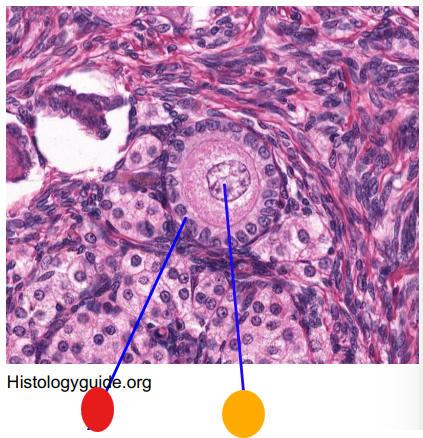

red

tunica albuginea

orange

primordial follicles

red

primary follicle

orange

secondary follicles

what is this

tertiary follicle